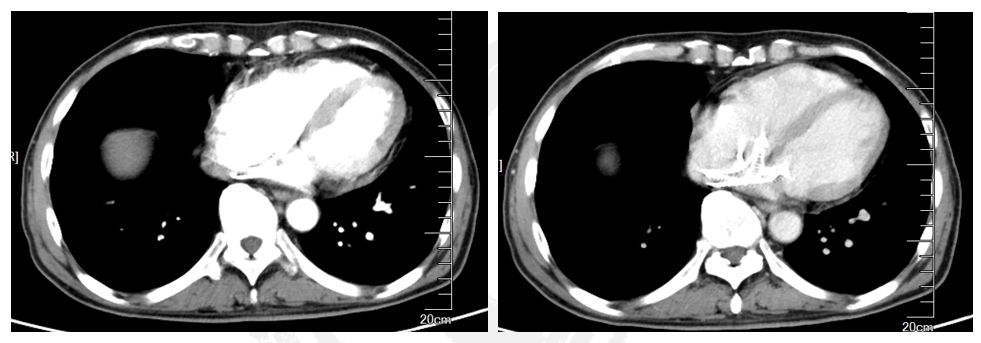

影像学检查:肝右叶见团块状稍低密度,内可见多发分隔,肝内瘤体内可能存在具有活性的瘤体组织

CNLC IIIa能否接受手术治疗?